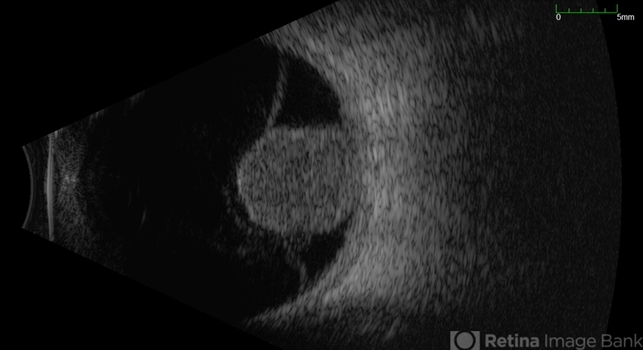

Choroidal melanoma

Choroidal melanoma appears on B-scan as a dome-shaped or mushroom-shaped, solid, highly reflective mass that shows internal low-to-medium echoes and may cause acoustic shadowing behind the lesion.